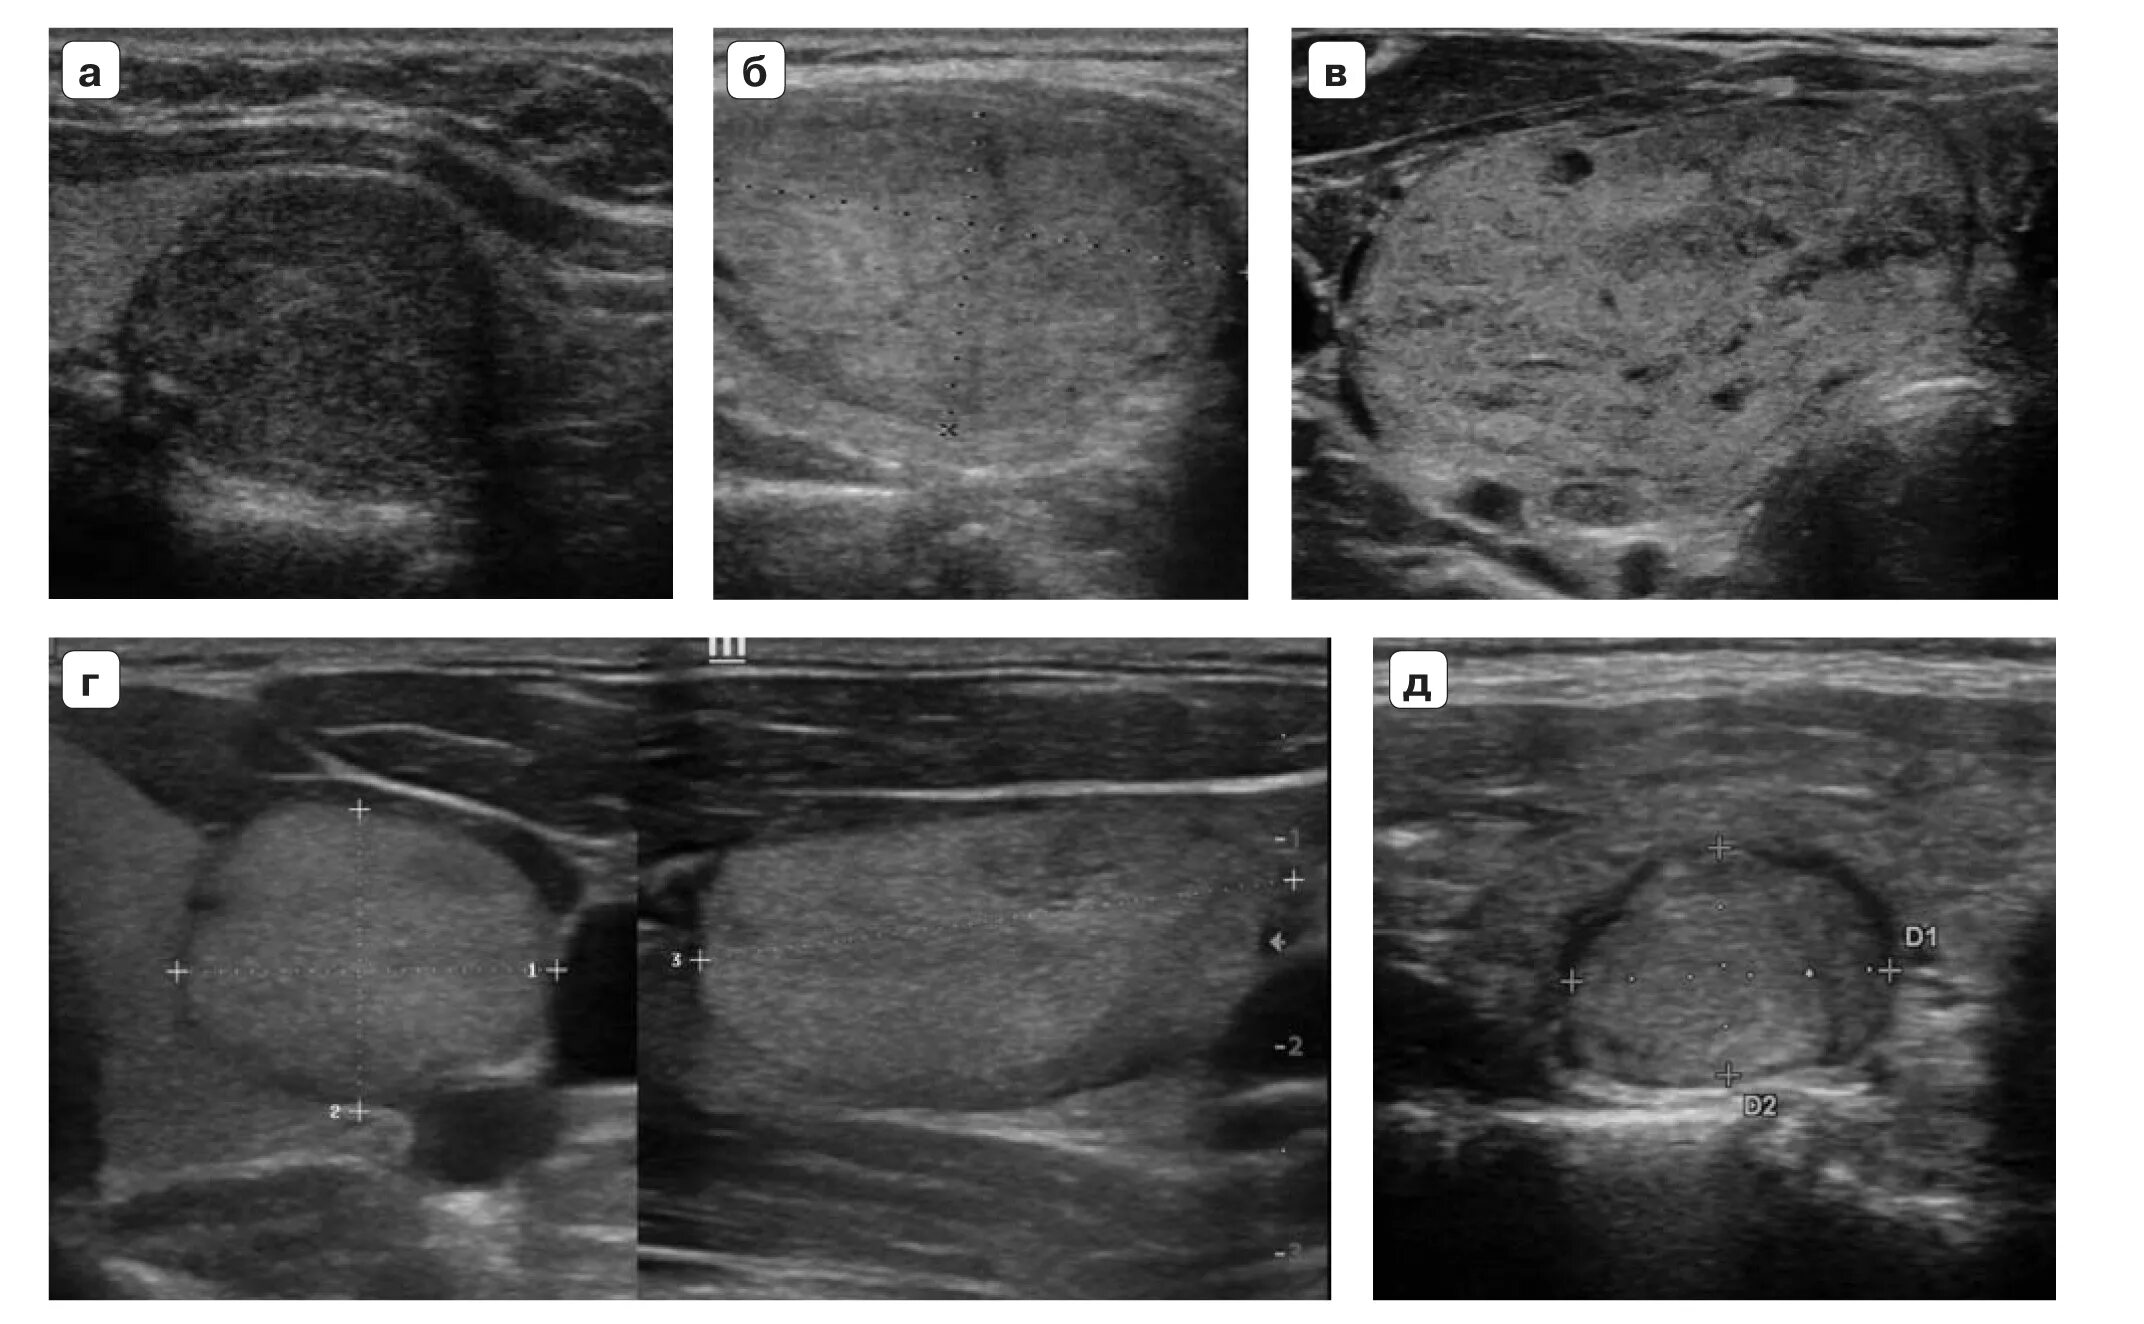

Узел ti rads